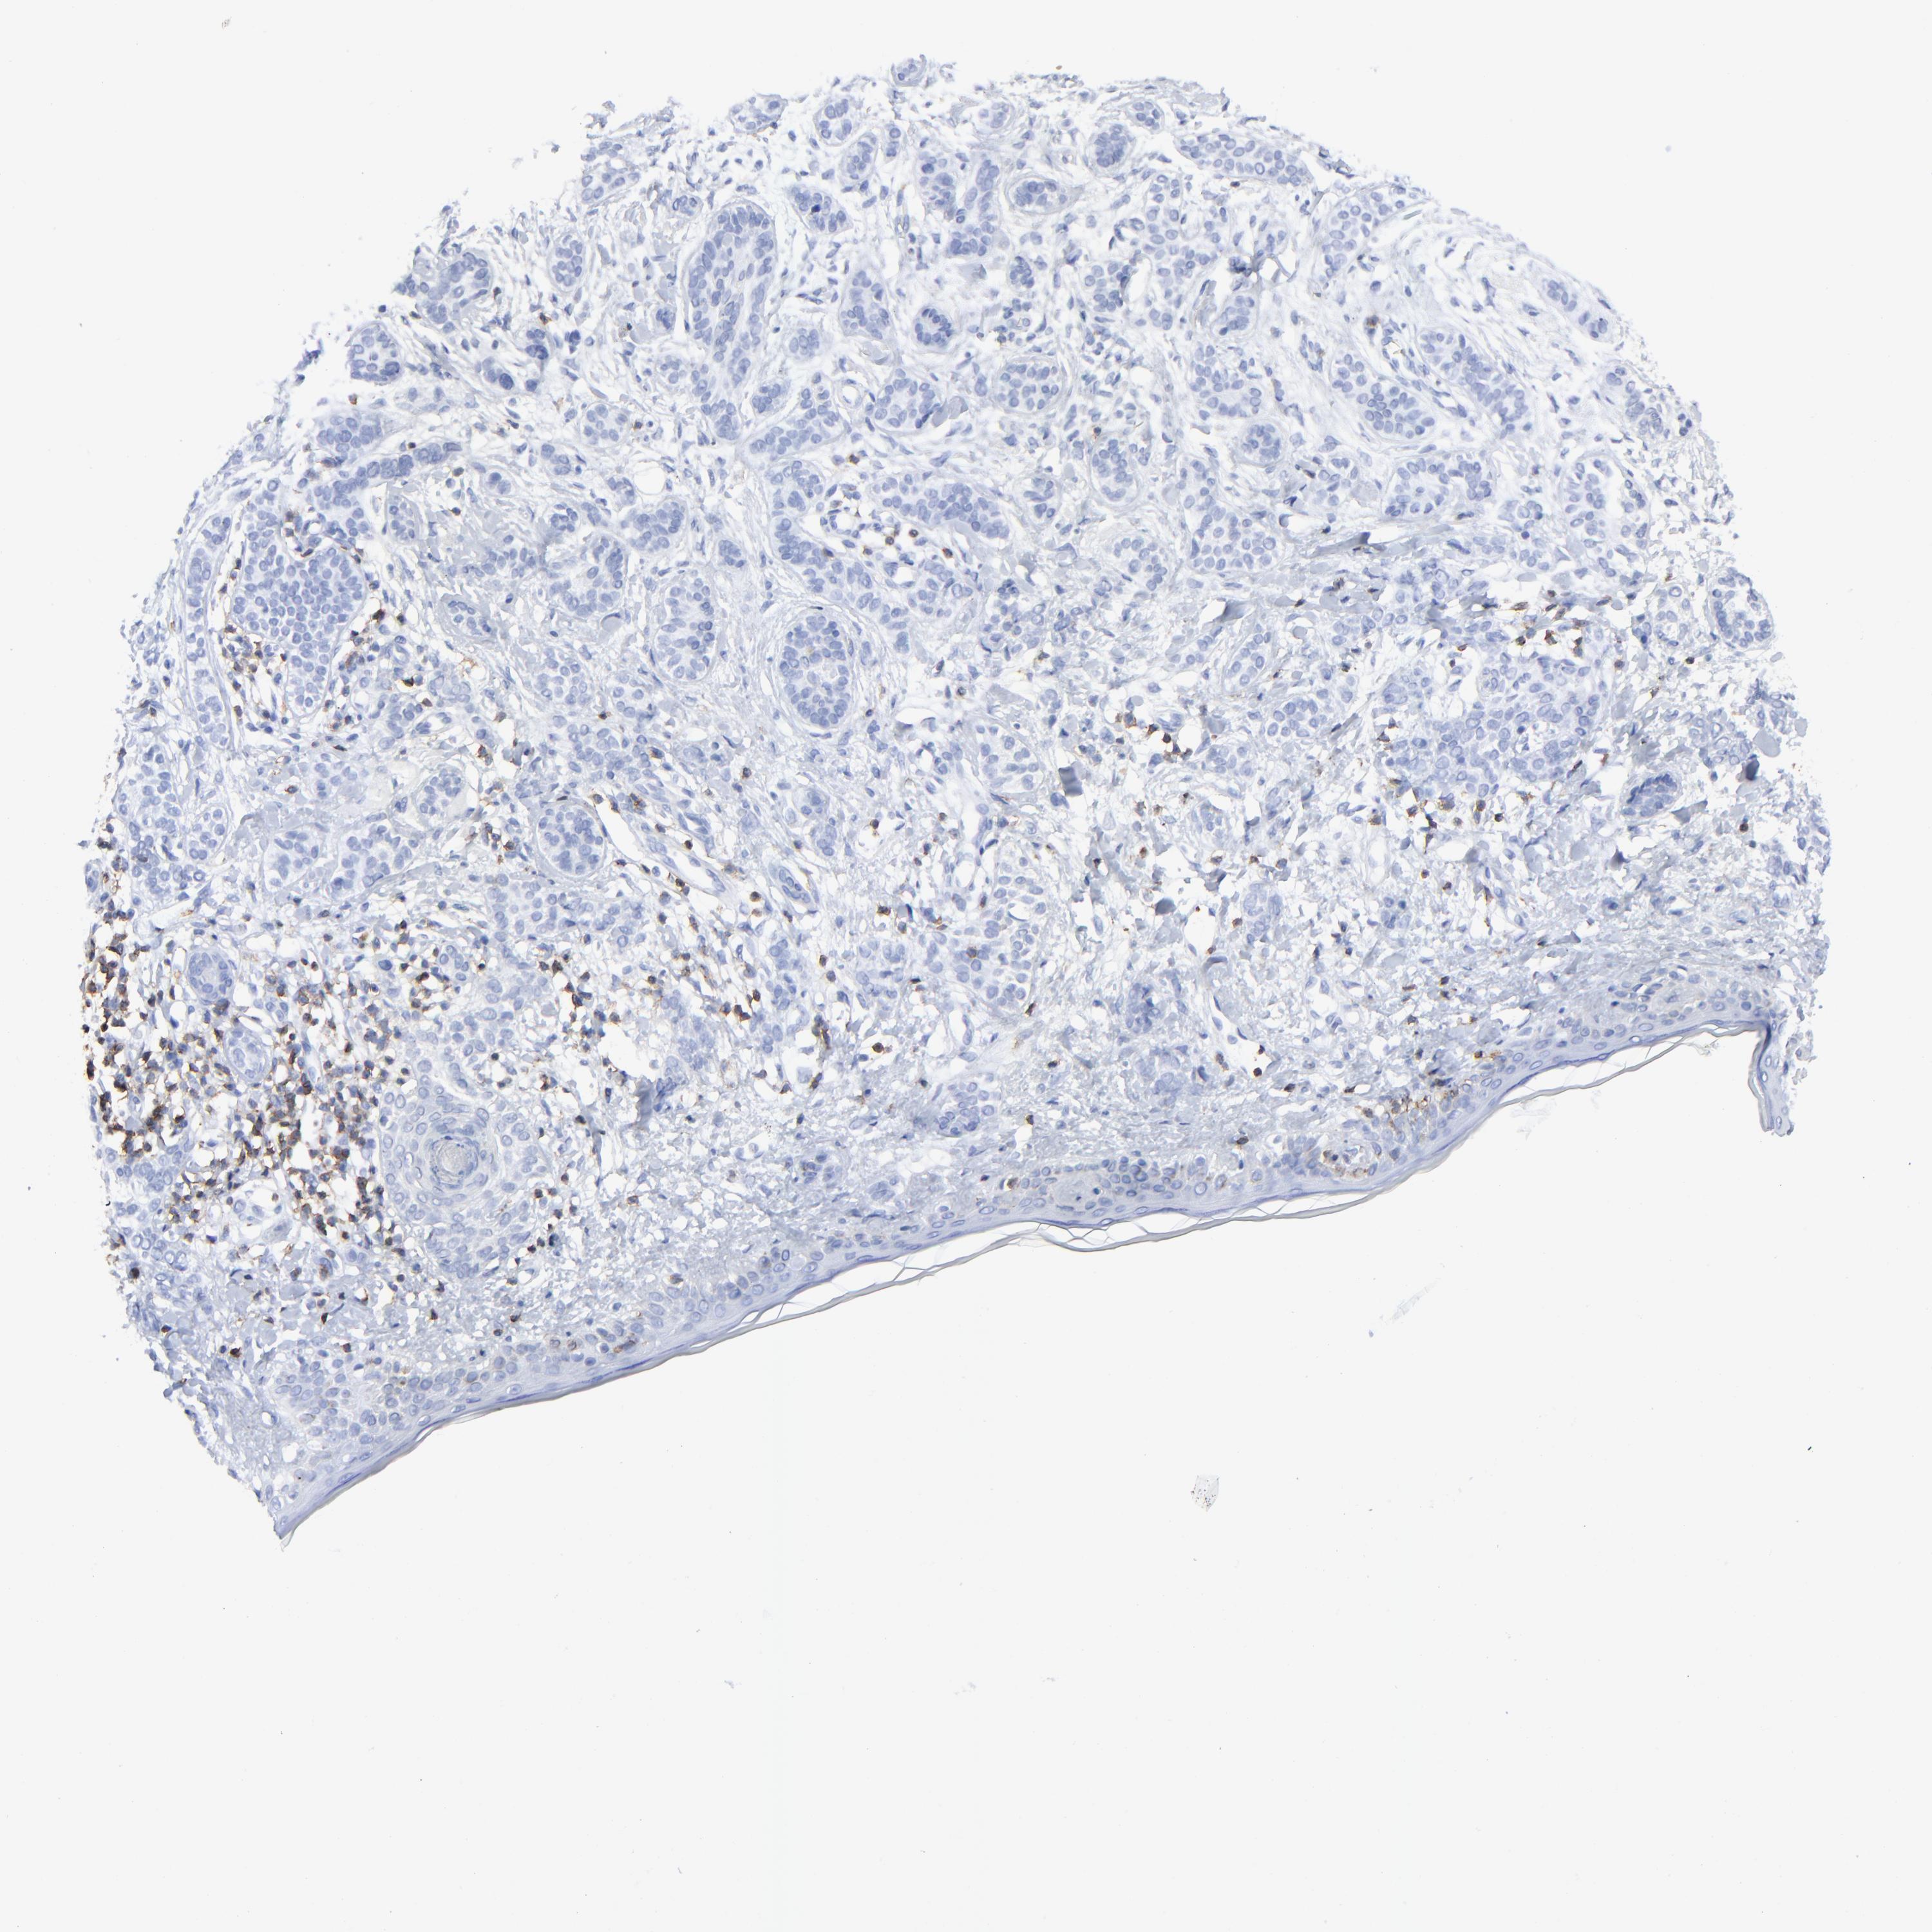

SKIN CANCER - Protein expressioni

A mouse-over function shows sample information and annotation data. Click on an image to view it in a full screen mode. Samples can be filtered based on level of antibody staining by selecting one or several of the following categories: high, medium, low and not detected. The assay and annotation is described here.

Antibody staining in the annotated cell types in the current human tissue is reported as not detected, low, medium, or high, based on conventional immunohistochemistry profiling in selected tissues. This score is based on the combination of the staining intensity and fraction of stained cells.

Each image is clickable and will lead to virtual microscopy that enables deeper exploration of all samples and also displays staining intensity scores, fraction scores and subcellular localization as well as patient and tissue information for each sample.

Antibody HPA003494

Antibody CAB003816

Staining

High

Medium

Low

Not detected

Intensity

Strong

Moderate

Weak

Negative

Quantity

>75%

75%-25%

<25%

None

Location

Nuclear

Cytoplasmic/membranous

Cytoplasmic/membranous,nuclear

Squamous cell carcinoma, NOS

Basal cell carcinoma